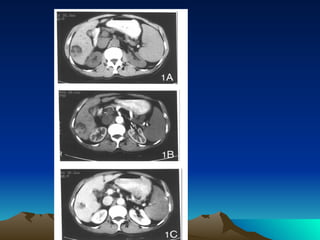

Ultrasound plays a significant role in screening and early detection of HCC , can detect 80% of tumors, tumors larger than 2cm can be found. It is a noninvasive examination and available for follow-up or screening, is a routine examination in chronic disease patient. CT&enhanced CT may find tumor less than 1cm ,enhanced CT aimed at diagnosing HCC take advantage of the hypervascularity of these tumors  and may differentiate from hepatic anginoma and other liver disease MRI  DSA  ECT  PET  Laparoscopy, percutaneous fine needle biopsy are also available. But the needle aspiration may add some hazard for hypervascular masses which can cause hemorrhage.

Computed tomography (CT) or magnetic resonance imaging (MRI) should be performed to better define the extent and number of primary lesions, vascular anatomy, vessel involvement, and extrahepatic disease. Helical CT or MRI should include early arterial phase enhancement.

Ultrasound plays asignificant role in screening and early detection of HCC , can detect 80% of tumors, tumors larger than 2cm can be found. It is a noninvasive examination and available for follow-up or screening, is a routine examination in chronic disease patient. CT&enhanced CT may find tumor less than 1cm ,enhanced CT aimed at diagnosing HCC take advantage of the hypervascularity of these tumors and may differentiate from hepatic anginoma and other liver disease MRI DSA ECT PET Laparoscopy, percutaneous fine needle biopsy are also available. But the needle aspiration may add some hazard for hypervascular masses which can cause hemorrhage.

Computed tomography (CT)or magnetic resonance imaging (MRI) should be performed to better define the extent and number of primary lesions, vascular anatomy, vessel involvement, and extrahepatic disease. Helical CT or MRI should include early arterial phase enhancement.